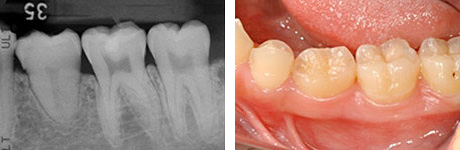

移植後4年。親知らずが第一大臼歯の代わりを担っています。

4年後。移植後に根が少し成長しているのが分かります。歯の神経もつながっています。